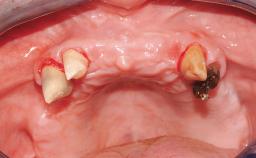

Immediate Loading of Six Implants in the Mandible and Six Implants in the Maxilla and Final Restoration with Full-Arch CAD/CAM Metal Framework FDPs Involving Digital Planning and Guided Surgery

Immediate loading of dental implants is increasingly popular with clinicians and patients. The idea of delivering a restoration directly after implant insertion,combined with a less invasive procedure (flapless protocol), has made treatment protocols involving dental implants more accessible to dentists and patients. However,immediate-loading concepts require sophisticated and exact planning. To facilitate this, conventional panoramic tomographs and periapical radiographs are often taken with the patient wearing a radiographic template simulating the preoperative prosthetic design. However, these radiographs do not provide all the necessary information. In addition, some protocols call for conventional surgical templates fabricated on the diagnostic cast. These will inform the bone drilling points and drill angles, but do not reference the underlying anatomical structures or provide exact 3-D guidance.

Case Type Edentulous Maxilla

Soft Tissue Contour and Volume Slightly compromised